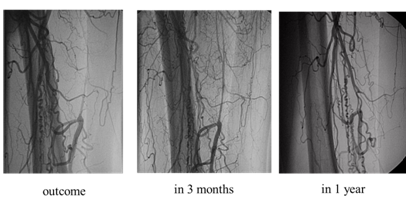

Paresthesia in the right foot at rest have disappeared, the walking distance, indicators of ABI and TcO2 on foot has increased (Table 1). At annual control surveys in the remote period the achieved result is stable. According to an angiography of the right lower extremity the collateral network in the pool of a deep femoral artery of the right lower extremity has significantly increased (+2 on classification of Tateishi-Yuyama published in 20025) in comparison with an initial picture (Figure 1). During the entire period of observation of pathological states and diseases it hasn't been established.

Figure 1 Results of angiography of the right lower extremity initially, in 3 months and in 1 year after autotransplantation of bone morrow endotelioblasts of CD133+.